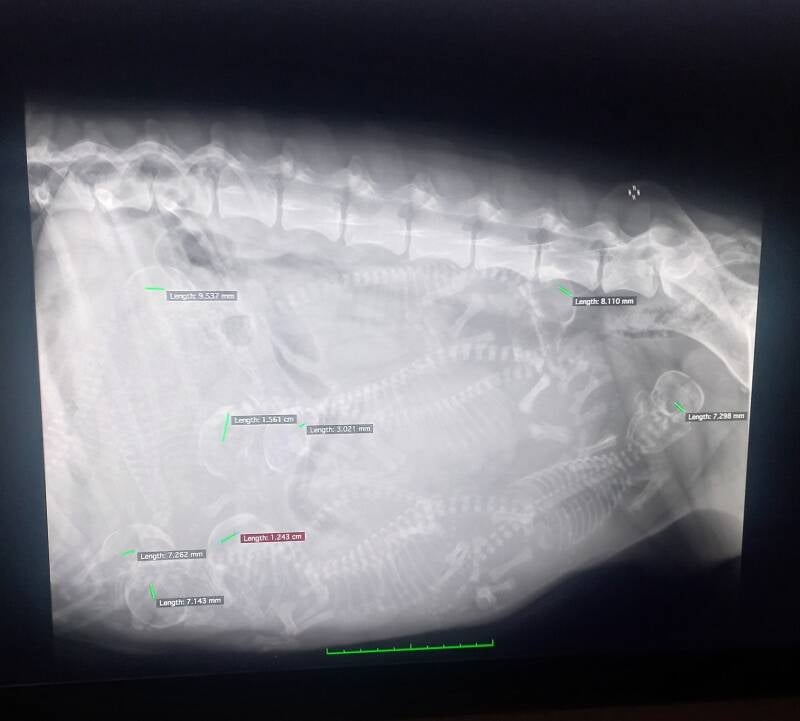

Nox heeft 8 pups in haar buikje🥰

« Vorige Nox krijgt een buikje Nox is bevallen op 25 juli Volgende »